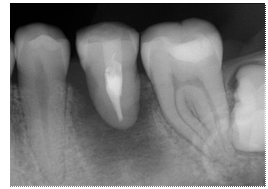

exploración clínica (Figura 1 A) y radiográfica (Figura 1 B), se observó el

órgano dental 36 con tratamiento de conductos presente y lesión extensa que

comunica con furca; el pronóstico es pobre, por lo que se toma la decisión

llevar a cabo la extracción de la pieza dental.

Figura 1.

A) Fotografía clínica preoperatoria. B) Radiografía periapical

inicial.